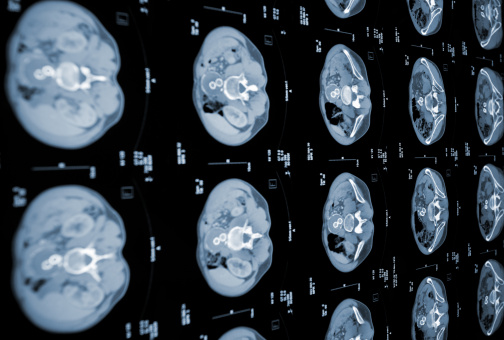

- 영상 검사: 초음파, CT 스캔, MRI 등을 통해 종양의 위치와 크기를 확인